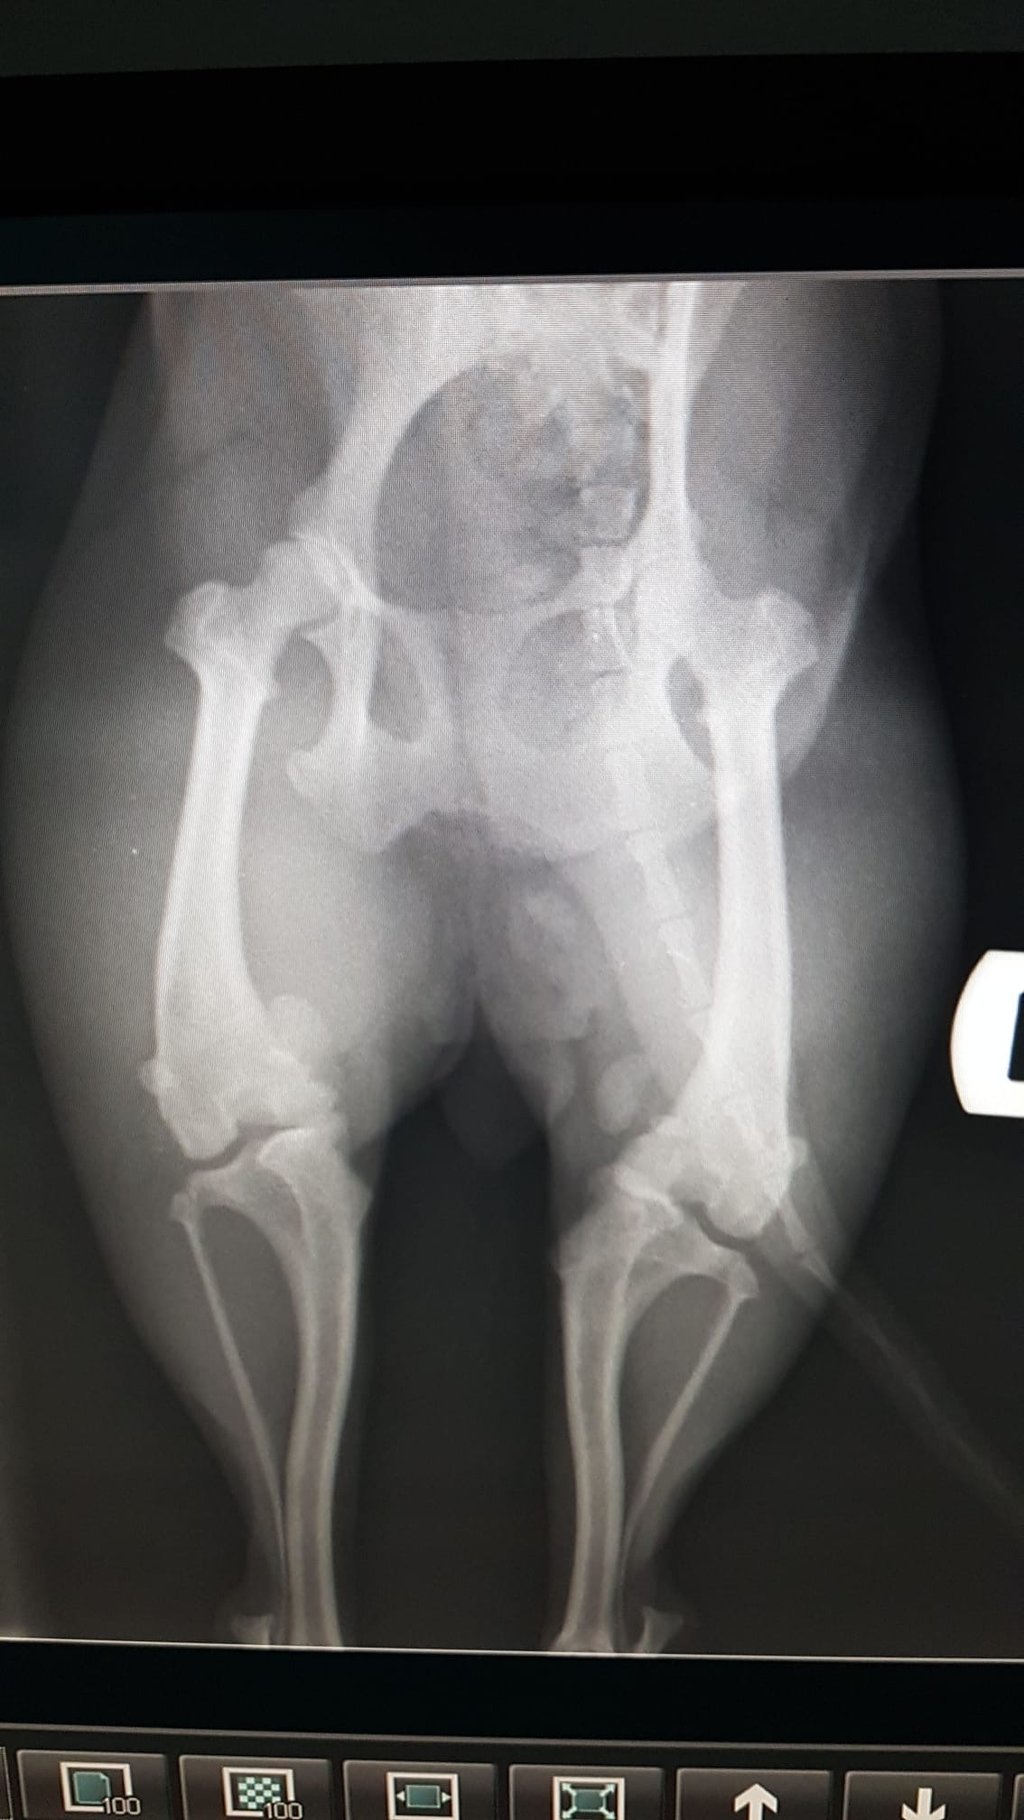

Nach dem Röntgen wurde eine Patellaluxation der Klasse IV diagnostiziert. Das ist eine Verlagerung der Kniescheibe, die aus ihrer Gleitrinne springt und so den natürlichen Bewegungsablauf beeinträchtigt. In den meisten Fällen ist eine Operation nötig, um die Kniescheibe in ihre ursprüngliche Position zurück zu führen und dort zu halten. Zusätzlich müssen Korrekturen von Unter- und Oberschenkel vorgenommen werden, um die Anatomie so weit zu verändern, dass die Kniescheibe dauerhaft in ihrer Führungsrinne verbleibt. Hierbei wird aus krummen Knochen ein Keil gesägt und der Knochen wird gerade wieder zusammengeschraubt (Osteotomie).